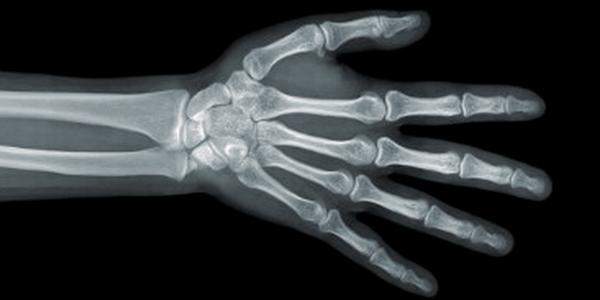

Рентгенограмма кисти руки

Рентген кисти руки используется с целью определения стадии скелетного роста пациента. Рост скелета человека происходит неравномерно в различные возрастные периоды. Весь период от рождения до завершения роста можно разделить в зависимости от интенсивности роста на 3 стадии: * Инфантильная фаза роста (от рождения до 3-4 лет). Интенсивность роста самая высокая, постепенно падает; * Ювенильная фаза роста (с 3-4 лет до 10-11 лет). Интенсивность роста постоянна в течение всей фазы, к концу периода несколько снижается, достигая «препубертатного минимума роста»; * Пубертатная фаза (с 10-11 до 16-17 лет) - пубертатный или адолесцентный скачок скелетного роста. Интенсивность роста возрастает, достигая максимума у девочек в среднем в 12 с половиной лет, у мальчиков в среднем в 14 лет. Затем интенсивность снижается, и скелетный рост завершается.